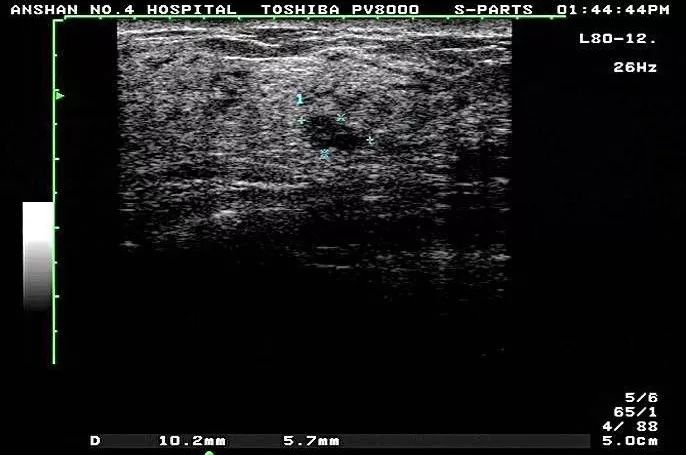

超声表现

1、二维图像表现

1)、患侧乳腺腺体层明显增厚,回声减低;

2)、乳腺导管尤其是乳晕区主导管不同程度的扩张,扩张的导管内隐约可见实性回声,为乳汁潴留的沉积物;

3)、形成脓肿时表现为腺体层内的无回声,壁厚,内壁凹凸不平,囊内有沉积物回声,腺体层增厚,乳腺区导管扩张,为乳汁潴留所致,脓肿壁厚,内壁凹凸不平,壁上血管的多普勒为低阻力型。